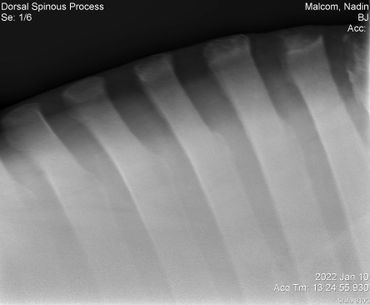

Update 03/04/2022 Billie Jean kept showing some severe sensitivity every time we touched her on her withers and along her spine so back in January we had x-rays taken to check for kissing spine. Everything looked great so we treated her for ulcers with Gastrogard paste and Sucralfate for 7 days.

Her vet bill from January 10 was $445